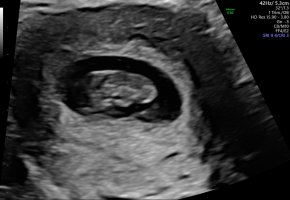

Skikkelig fint bildeVis vedlegget 382557

Dette var vel 7+5, hode, rumpe, arm og fot ses her. Ikke mye en se så tidlig, men vi var for å se etter hjerteslag og det fikk vi se.